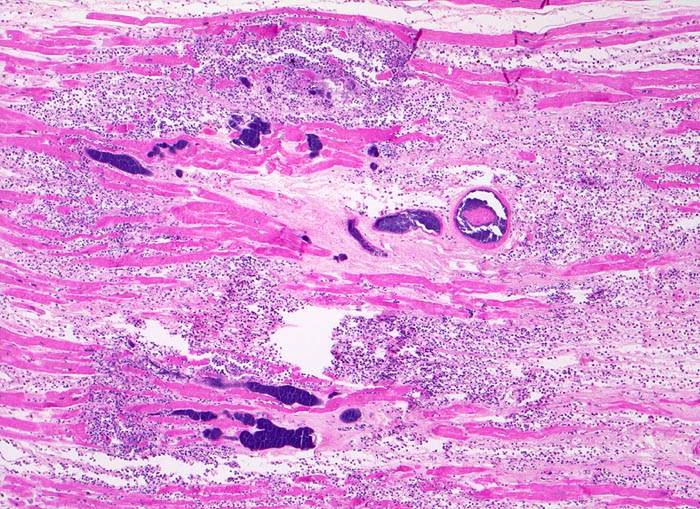

AP/ Pyämische Myokarditis

Pyämische Myokarditis

Morphologische Merkmale:

• Blaue Flecken in der Übersicht. Diese entsprechen Ansammlungen von neutrophilen Granulozyten (Mikroabszesse).

• Links unten im Bild sind mehrere Arterien mit intra- und perivaskulären Kokkenbakterien und neutrophilen Granulozyten erkennbar.